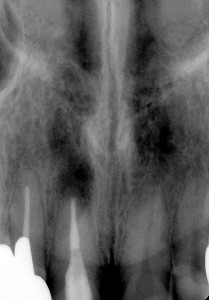

手術前 手術後 手術後1年

確かにしっかり治ってくれています。患者さんも喜んでくれています。